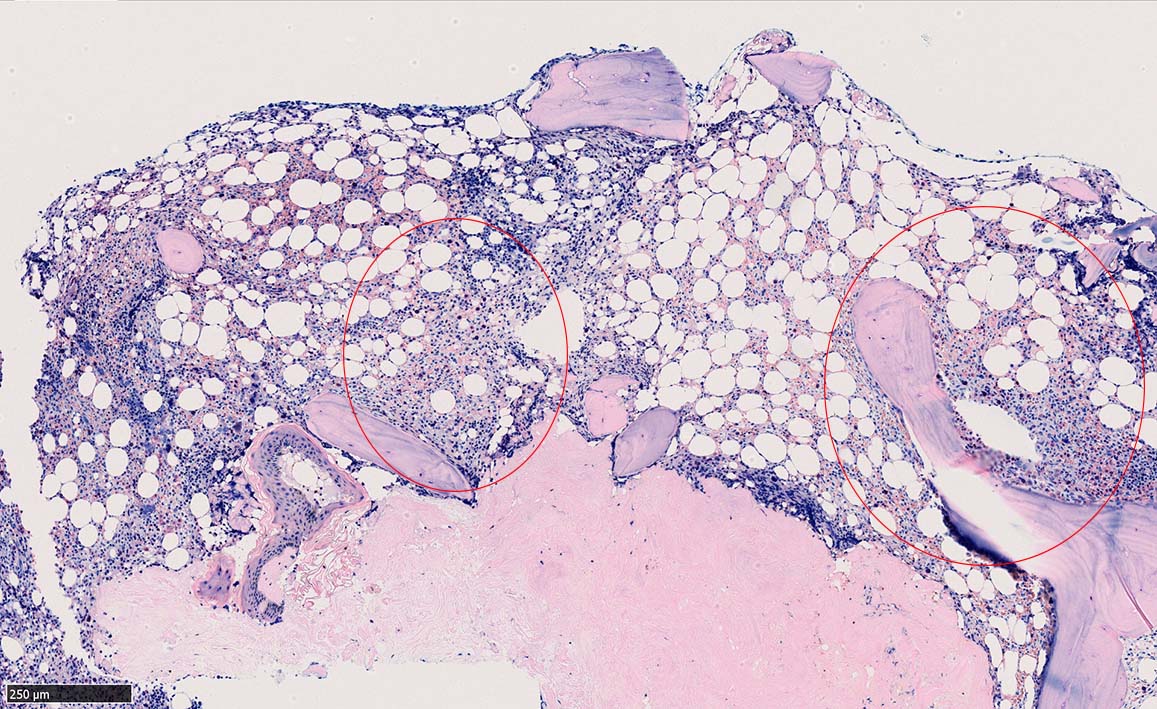

骨髄生検

bone marrow trephine biopsy: dry tapのため骨髄生検が行われる. cellularityは40-80%とhypercellular marrow. 流れのある細胞配列は線維化を疑わせる.

ASD-G 低倍率所見では赤芽球血島は幼若赤芽球の集簇巣が散在する, 顆粒球系細胞(ASDに赤く染色される)は減少,granulopoietic hypoplasiaを呈する.疎な集簇を示すmast cellsの増加がある.

ASD-G陰性の細胞がびまん性に増加しているように見える.

ASD-Giemsa陰性の細胞がシート状に増殖する. 核はクロマチン濃染, 核小体は不明瞭.類円形, 卵円形, くびれを持つ多稜形核, 長円形いびつで屈曲した核, など多彩. 細胞質は淡清色調, 広く淡明. 赤芽球血島は幼若赤芽球のみで形成される異形成像を示す. やや離れて成熟赤芽球が疎な集簇を示す.

Ag染色では, 疎な弾性線維が増生し,増殖細胞を小胞巣状に分画するいわゆる「lymphomatoid pattern」を呈する. 本例では, Mgkに異形成所見がある.